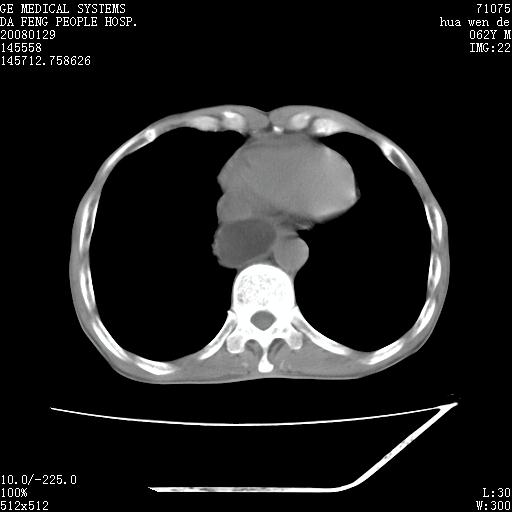

男性,67岁。作肺部检查时发现

考虑:胸腔胃并支气管瘘(并发吸入肺炎,肺脓肿形成)。

理由:1、右上肺内病灶,空洞形成,有液平。

2、肺内多处炎症。

3、前段肺内炎症,支气管引流通畅,与肿块无关系。

1.整个食管扩张,未见明显占位性病变,贲门区亦未见明显占位病变,考虑:贲门失驰缓症;

2.右上肺病变边缘可见毛刺,囊壁厚度不均匀,周围境界较清楚,未见炎性渗出性影,右上肺外带可见片状影,边缘不清,考虑:肺癌伴空洞形成、右上肺炎。

食管全程扩张,壁均匀不厚,喷门失弛缓症

右上肺空洞可见液平,临近肺野磨玻璃密度,考虑1.结核2.脓肿

贲门失驰缓症.肺部感染伴脓肿形成。支持!是否吸入性要结合临床诊断,我们影像是看不出来的。但胸腔胃能排除(1.没有手术史支持,2.双侧胸廓对称,胸壁、肋骨及胸膜规整,3,食管壁明显扩张内壁光滑,胸腔胃黏膜皱襞多较厚)。